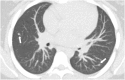

Hamartomas are tumours composed of mesenchymal tissues such as cartilage, fat, connective tissue and smooth muscle and can be found in virtually any organ system. These masses commonly develop sporadically, but are also seen in certain syndromes such as tuberous sclerosis or Carney triad. While their imaging appearance varies depending on the organ they arise from, findings are usually unique and a diagnosis can be confidently made. Radiologists must be aware of the clinical and imaging presentations of these lesions with the particular goal of avoiding unnecessary studies or invasive procedures. Furthermore, knowledge of common syndromic entities is crucial, as the radiologist may be the first to suggest the diagnosis.